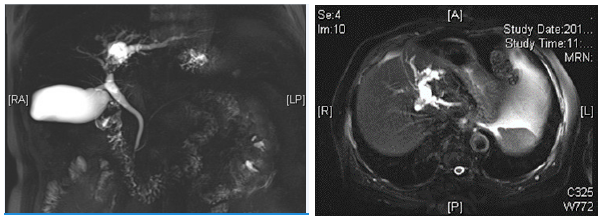

On January 16, 2018, a 76-year-old male patient was admitted due to “upper abdominal pain and discomfort for over 1 week”. The patient presented with mild jaundice, no rigor and hyperpyrexia. Laboratory tests: glutamyl transpeptidase (GGT): 578U/L; alkaline phosphatase (ALP): 149U/L; Total bilirubin: 25.20umol/L; Indirect bilirubin: 20.10umol/L, CA125:8.39U/ ml, CA199:12.99U/ml. Imaging examination: abdominal enhancement MR & MRCP: nodular abnormal signal lesion about 1.7 × 1.1cm was observed in the left hepatic duct near the hepatis porta, and enhancement was observed in the enhanced scan; the upstream intrahepatic bile duct in the left lobe of the liver was significantly expanded. Intraoperative findings: The patient underwent left hemi hepatectomy & cholecystectomy. During the operation, there was free tumor embolus at the broken end of left hepatic duct. It was decided to perform common bile duct exploration. The upper segment of common bile duct was incised and removed the tumor. T-tube drainage was left in place after performing the choledochoscopy. Postoperative pathology: (left half liver and contents of bile duct cavity) intraductal papillary neoplasm, high grade, with total lesion area of about 1.1 × 0.7cm. Liver resection margin, gallbladder neck lymph node (1) and “Group 12” lymph node (3) showed no tumor. The patient was followed up for over 1 year after the surgery, without obvious abnormality (Figure 1).

Figure 1:MR + MRCP showing nodular filling defect in the left hepatic duct and the confluence of left and right hepatic ducts in the hilar region, and biliary dilatation in the left lobe of the liver.